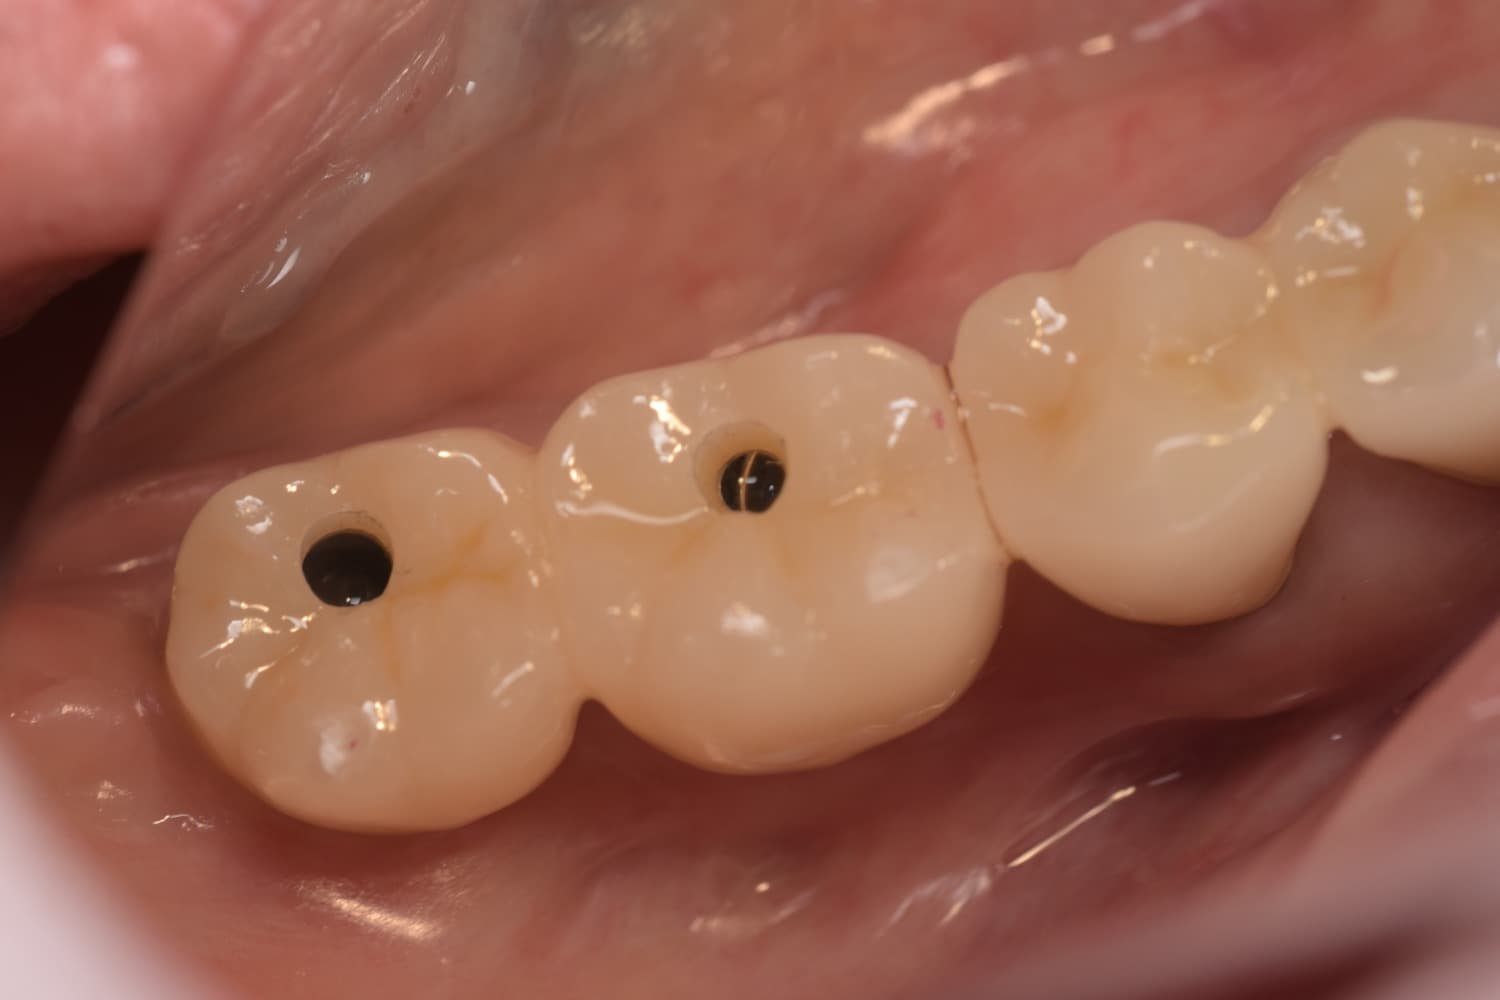

骨が薄い方のインプラント治療(50代女性)

Before

After

足りない分の骨を補いインプラントを埋入

年齢

50代

性別

女性

主訴

骨が薄くインプラントが入れられない

治療期間

6ヵ月

治療回数

8回

費用

100万円

副作用・リスク

術部の腫れ